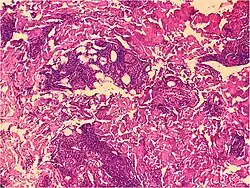

Psoriaform dermatitis

Examining multiple deeper levels is recommended if initial cuts do not correlate well with the clinical history.[2]

Psoriaform dermatitis typically displays:[2]

- Regular epidermal hyperplasia, elongation of the rete ridges, hyperkeratosis, and parakeratosis.

- Usually:A superficial perivascular inflammatory infiltrate

- Often: Thinning of epidermal cells overlying the tips of dermal papillae (suprapapillary plates), and dilated, tortuous blood vessels within these papillae

Further histopathologic diagnosis is performed by the following parameters: